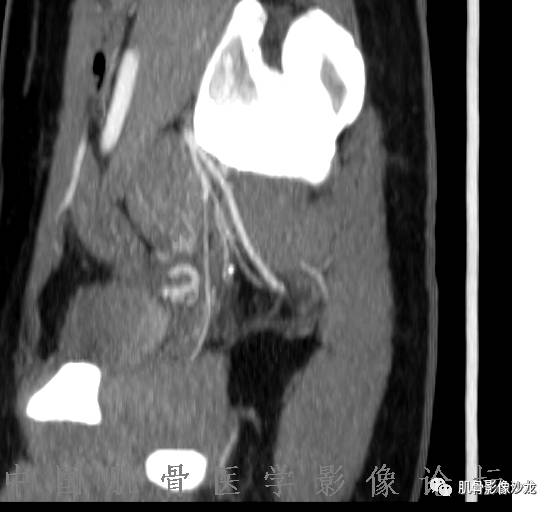

1、软骨肉瘤可以有膨胀性骨质破坏(病例3,4),可以有溶骨性骨质破坏(病例2),局部皮质因为破坏变薄,中断 ;

2、软骨基质T2WI高信号,软骨小叶分叶状,也就会出现高老师提到的骨内膜扇贝形压迹。一般认为骨内膜扇贝形压迹超过骨皮质厚度的2/3是软骨肉瘤在长管状骨的特征性表现。如上图。3、软组织肿块或肿胀;

5、增强后进行性延迟,不均匀分割状强化, 会强化的纤维间隔,软骨小叶不会强化,关于老师们说到的钙化,软骨肉瘤不一定会有钙化 。

雪舞 :1、骨恶性肿瘤的发病率排名:多发骨髓瘤、骨肉瘤和软骨肉瘤

2、软骨肉瘤的发病部位排名:最好发部位为髂骨,其次股骨、肱骨和脊柱。

郝大鹏: 软骨小叶常规时间不强化,延迟几个小时会强化。常规时间内强化的是小叶间隔